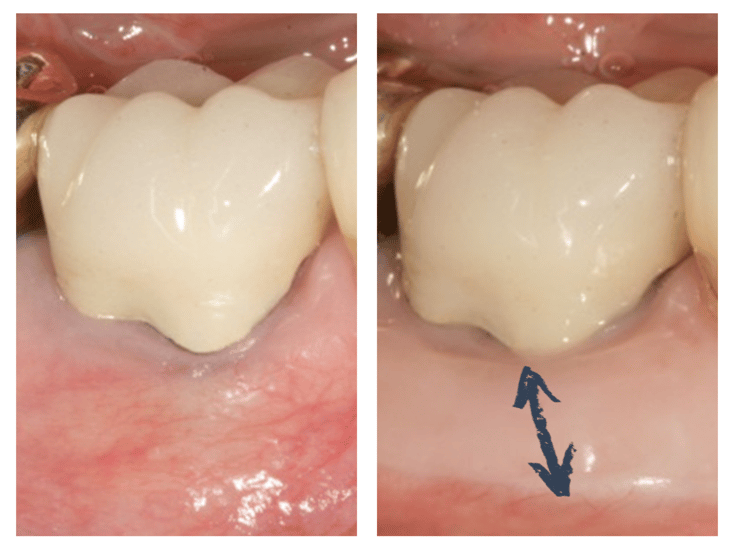

Recouvrement de la racine dénudée avec une greffe de conjonctif enfoui © ParoSphère

Figure 3 - Recouvrement de la racine dénudée avec une greffe de conjonctif enfoui © ParoSphère

Cette technique permet de repositionner la gencive dans sa position initiale, ou dans une position qui s’en rapproche, et permet d’augmenter l’épaisseur de cette gencive limitant ainsi le risque de récidive (Figure 3).

La greffe de tissu conjonctif est une technique plus récente, en constante évolution [9-12]. L'apport des micro-instruments permet aujourd'hui une approche moins traumatique, plus précise et plus esthétique. Une fois l’anesthésie locale effectuée, le parodontiste prélève un greffon à l'intérieur du palais en ouvrant un volet gingival. Il le positionne ensuite sur la partie dénudée de la dent touchée par la récession et le recouvre dans la mesure du possible en tractant la gencive par-dessus. Il fixe le greffon et la gencive dans la position voulue avec des points de sutures. Le volet ouvert au palais est ensuite simplement refermé avec des sutures, n'exposant pas de plaie à vif et diminuant ainsi les suites postopératoires.